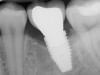

Fig 4. Increased probing depth around an implant with BoP indicates presence of peri-implant disease and the need for taking a radiograph.

Figure 4

Fig 5. Bone loss shown on radiograph confirms the presence of peri-implantitis and peri-mucositis.

Figure 5